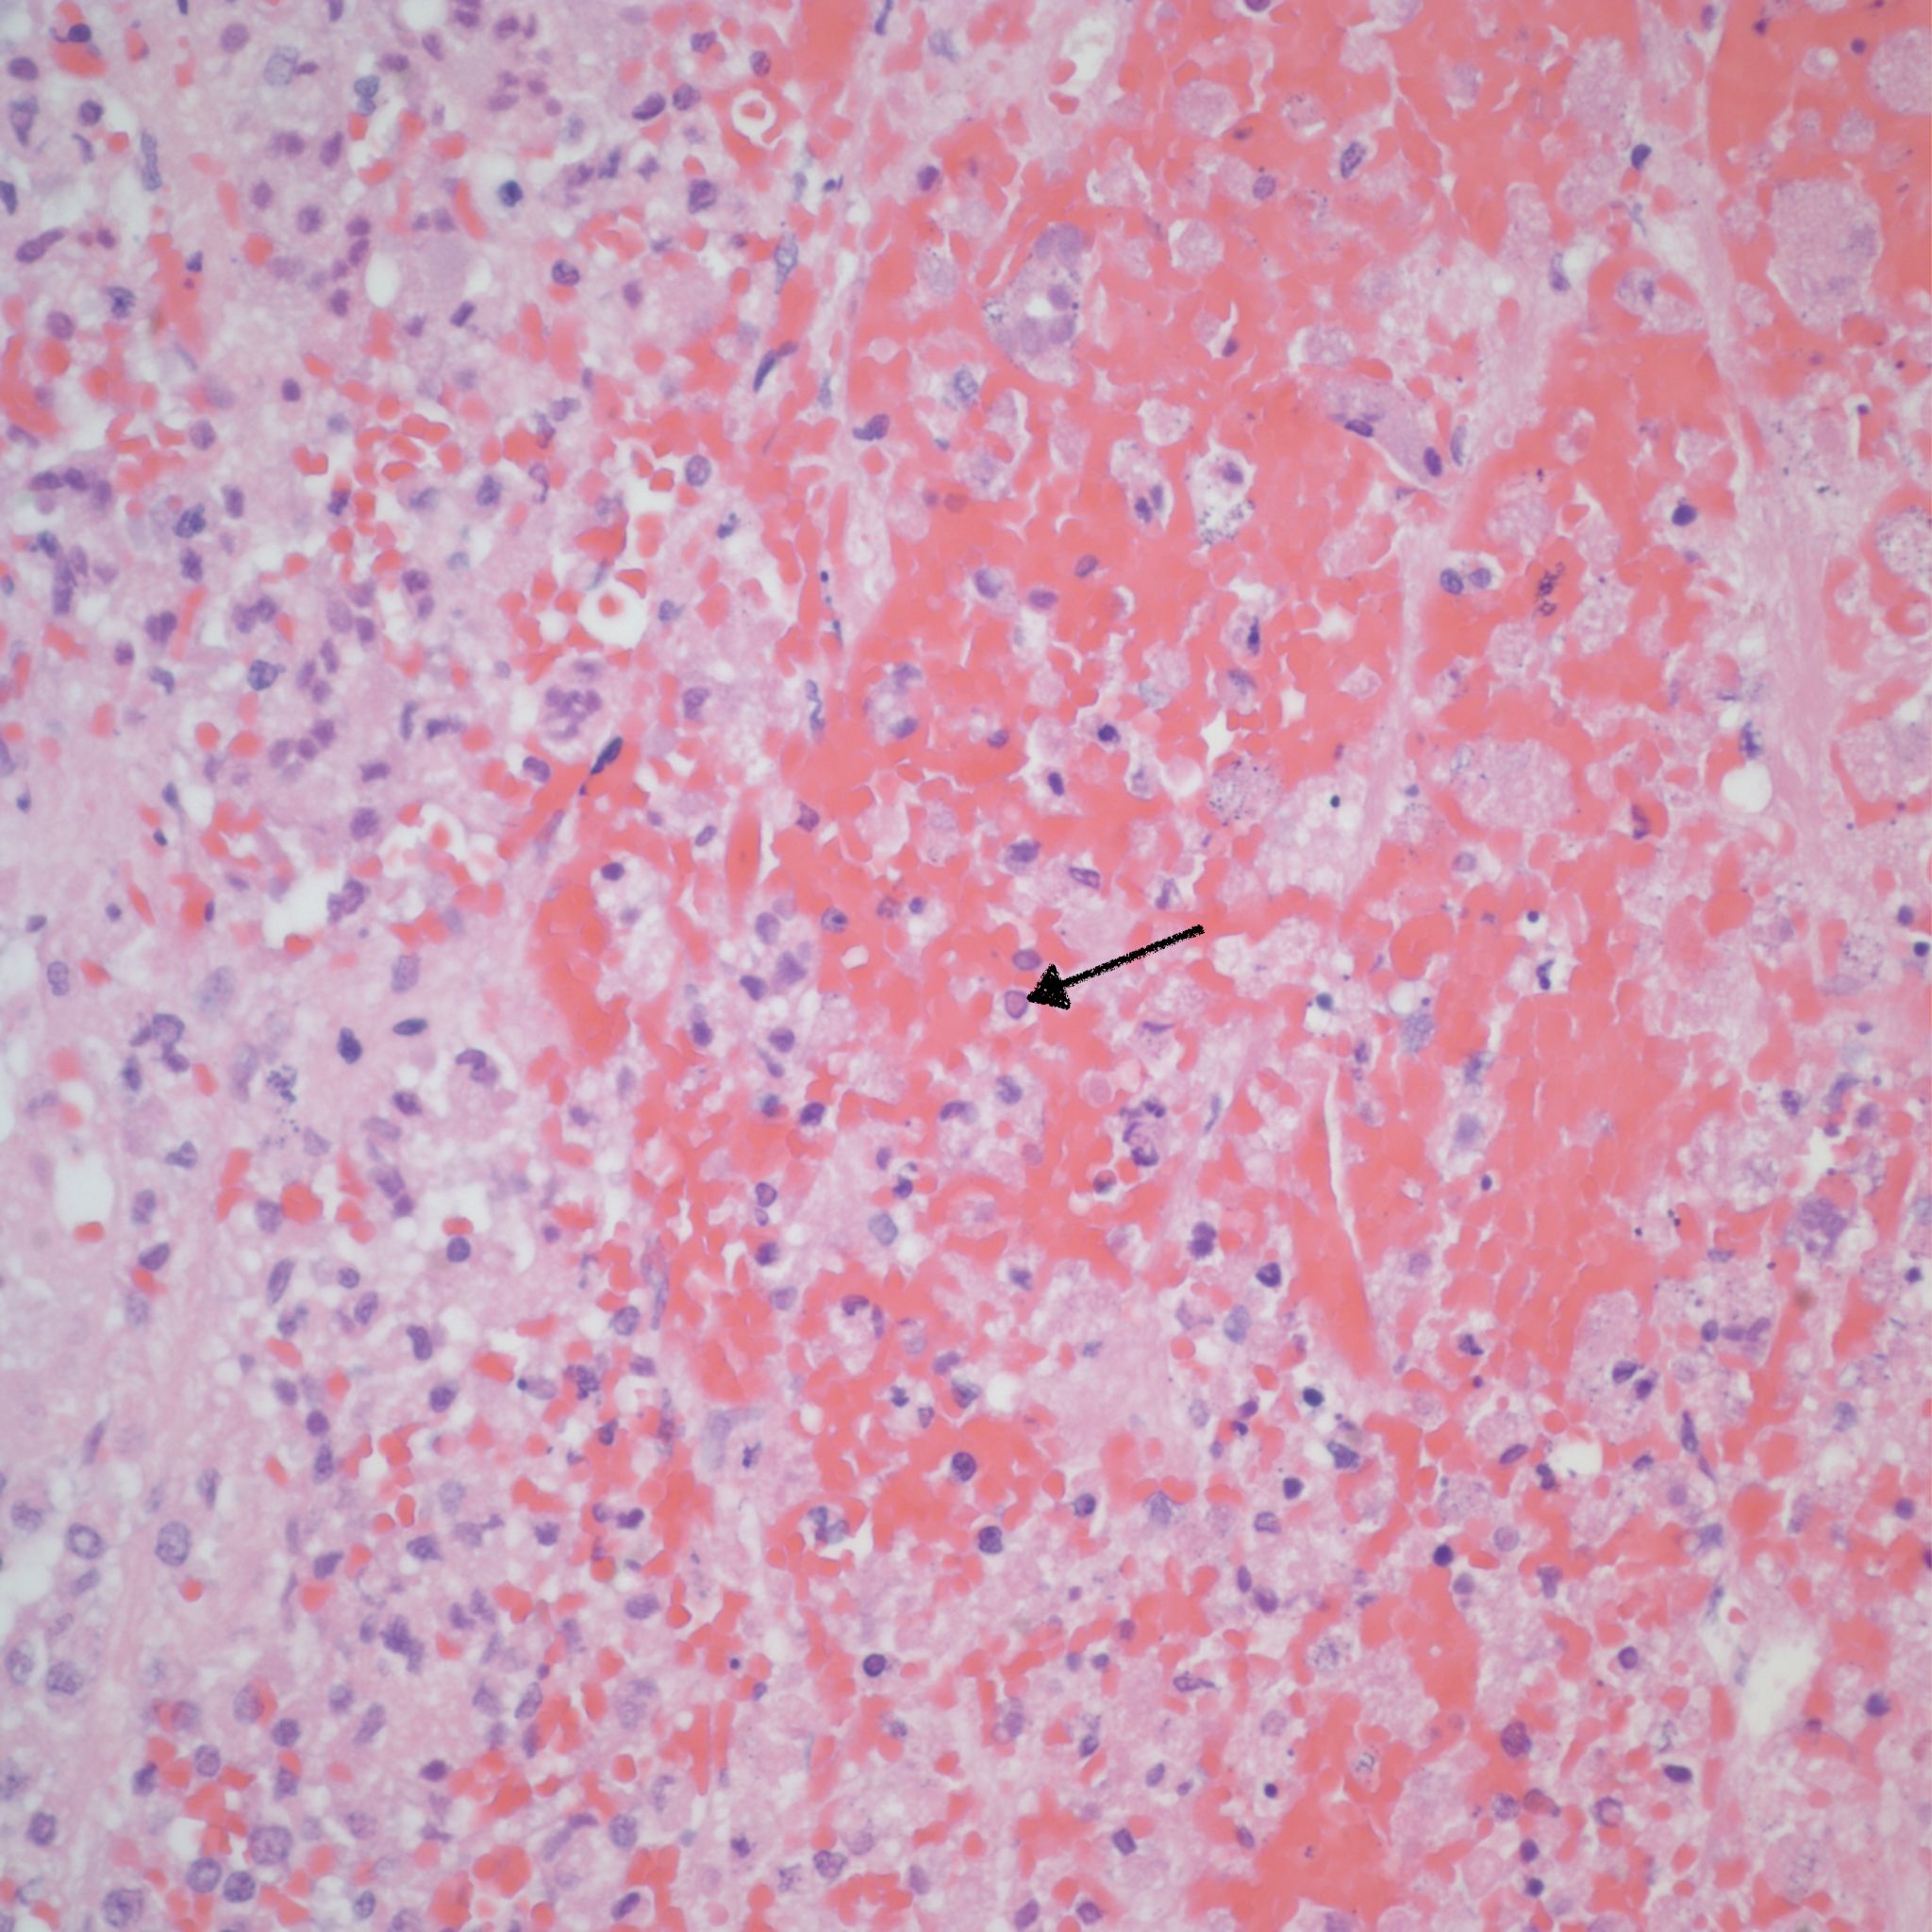

Medical students are likely to be aware of adrenal hemorrhage as a manifestation of septic shock with the Waterhouse Friderichsen hemorrhages with meningococcemia. In the fetus and newborn, the first manifestation of shock is likely to be either congestion/hemorrhage or fibrin thrombi. The fibrin thrombi were documented as a neonatal response to shock in infants with hypoplastic left heart syndrome [28] (Fig 9).

Before the advent of corrective surgery these infants died of cardiogenic shock in response to closure of the ductus arteriosus. Focal infarction an can also occur. Often in the adrenal the line between marked sinusoidal congestion and hemorrhage is hard to distinguish. The hemorrhage usually begins to obliterate the sinusoidal outline starting in the deepest fetal cortex. (Fig 10,11)

In the context of fetal infection, I accept adrenal hemorrhage as evidence of fetal septic shock similar to W-F hemorrhages, however, but I am unaware of evidence for this. A study by Jacques and Qureshi found that adrenal hemorrhage correlated with other evidence of acute asphyxia such as abruption, intrathoracic petechiae and lack of thymic involution[11]. Figs (12-14)

Fig 12-14: These are slides from a case conference. The first slide demonstrates the adrenal with hemorrhage. The next slide demonstrates the lung with extensive congenital pneumonia with overgrowth of pale basophilic cocci. The third slide demonstrates on the left a cluster of gram + cocci on the fetal membranes and a sparse maternal neutrophil infiltration at the junction of the chorionic epithelium and connective tissue (arrow) (Brown Gram). The right panel shows a similar cluster of cocci on the surface of the umbilical cord (H&E). The lung culture grew Group B beta hemolytic Streptococcus.